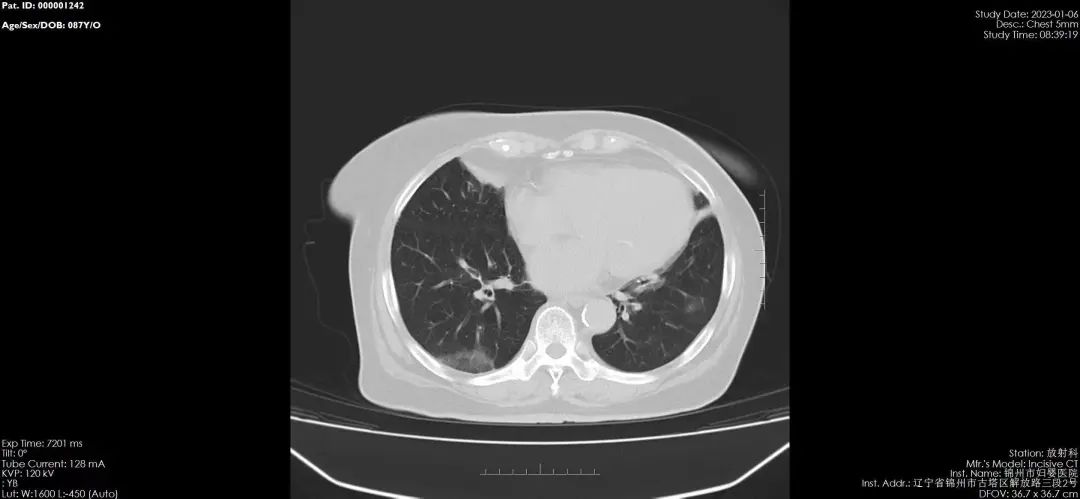

鉴于新冠病毒感染后容易出现肺部感染和肺部炎症等情况,很多感染者有肺CT检查的需求,为了让患者得到及时的检查,锦州市妇婴医院(妇幼保健院)积极开展成人及儿童的肺CT检查诊疗服务,并推出门诊优惠活动,费用降为210元,无需预约,即来即检。

医院24小时开诊,门诊全部科室均可开具肺CT检查,如结果异常,儿童直接在本院就诊,成人可持出具的报告和影像片到综合医院就诊。

新冠肺炎CT的影像学表现:在疾病的早期,患者可以出现多发的斑片影,为淡片状的渗出影。随着疾病的进展,双肺影像学会出现加重,为双肺、多肺叶、多肺段的渗出影,可以为间质性病变。

在病程7天左右,患者的肺CT可以出现加重,而导致双肺弥漫性的间质纤维性病变。重型和危重型病例可发生肺实变表现为白肺,患者出现呼吸衰竭,因此即便“症状较轻”也千万不能轻视。上呼吸道感染如果不及时治疗会进展肺部也会出现阴影,如咳嗽剧烈、伴有明显气短或者出现咳大量黄痰,甚至出现痰中带血、伴有反复发热、进行性加重的呼吸困难、胸痛等新发症状或原有症状加重时,应及时完善肺CT检查。